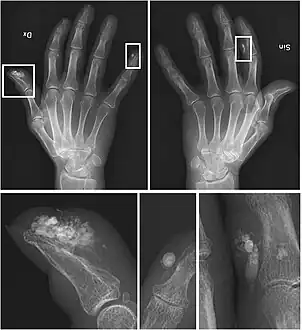

X-rays showing calcinosis in a woman with CREST syndrome

X-ray of subtle calcifications in CREST syndrome